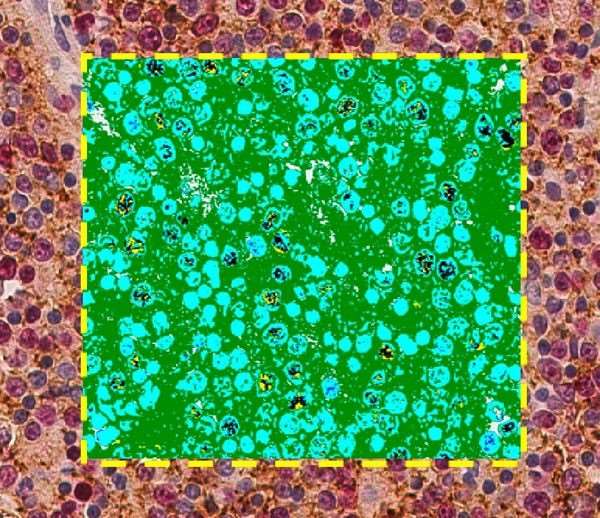

Aperio 細胞膜算法 - 快速細胞膜分析

Aperio 細胞核算法 - 計數和量化染色細胞核

Aperio 細胞質算法 - 準確的亞細胞 IHC 分析